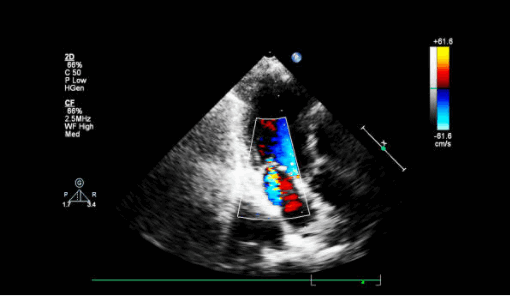

- Поместите цветной допплеровский сектор на митральный клапан и левое предсердие. Посмотрите есть ли струя митральной регургитации (высокоскоростной или турбулентный пятнистый поток в систоле)? Во многих случаях он будет направлен эксцентрически либо к передней, либо к задней стенке левого предсердия. Как правило, молотящая створка МК направляет струю MР в сторону от самой поврежденной створки.

Другой причиной внезапной артериальной гипотензии и отека легких у пациента в пери- и постинфарктном периоде является разрыв межжелудочковой перегородки. Дефект заставляет насыщенную кислородом кровь течь из левого желудочка в правый и смешиваться с деоксигенированной кровью. Дефекты межжелудочковой перегородки (ДМЖП) могут возникать в переднем отделе перегородки (лучше всего видно в парастернальных окнах) из-за переднего ИМ или в нижнем отделе перегородки (лучше всего в апикальном четырехкамерном и субкостальном окнах) в результате нижнего ИМ. Оба типа ДМЖП могут быть проверены на предмет использования парастернальных окон по короткой оси. Использование цветного допплера имеет важное значение для обнаружения этих разрывов на эхокардиографии, потому что разрыв ткани часто имеет щелевидную или змеевидную форму и может быть плохо заметен на одном только 2D-изображении.

- Поместите цветное допплеровское окно на межжелудочковую перегородку, особенно на любые акинетические участки или сегменты с пропаданием эхо-сигнала (анэхогенные зоны). Цветовой поток слева направо, проникающий через перегородку, указывает на ДМЖП.